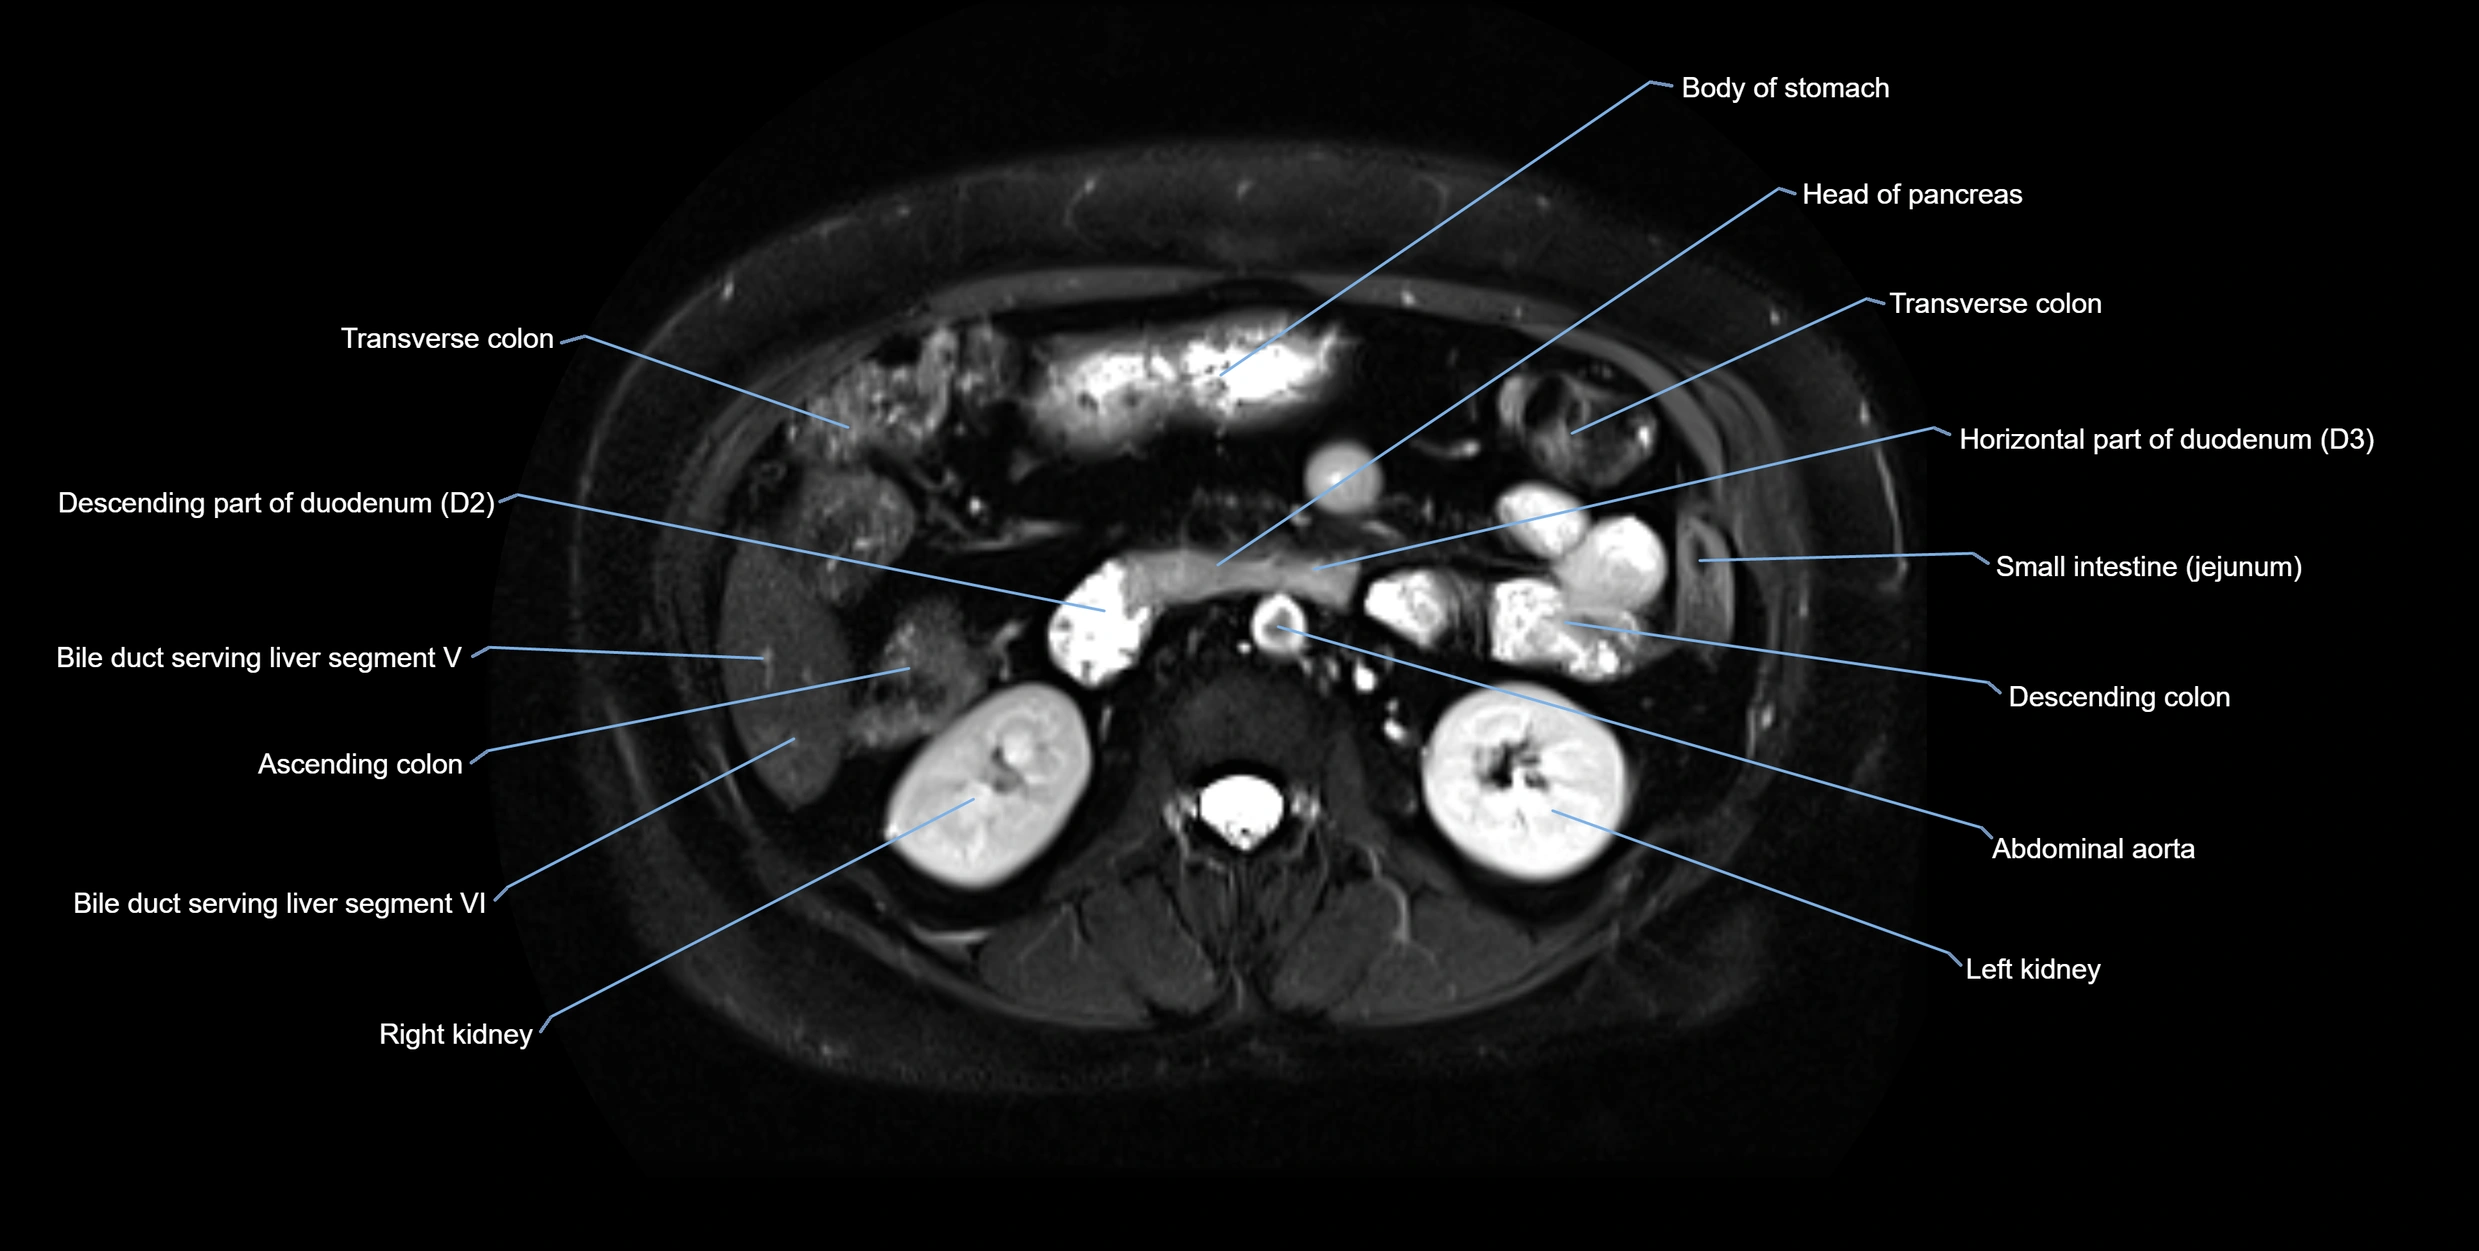

MRI image

image